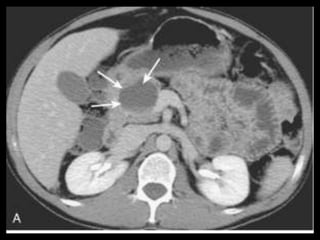

PANCREATITE AGUDA GRAVE

A administração de contraste IV é essencial,

especialmente em pacientes com PA grave, para

visualizar o pâncreas, diferenciar a glândula de

coleções líquidas adjacentes e do tecido

inflamatório peripancreático e demonstrar a

necrose pancreática.

Áreas focais ou difusas de realce diminuídas ou

ausente à TC contrastada dinâmica constituem

áreas de isquemia ou necrose.

TC tem precisão geral de 87% com S e E de 100%

para necrose extensa e 50% com áreas menores.